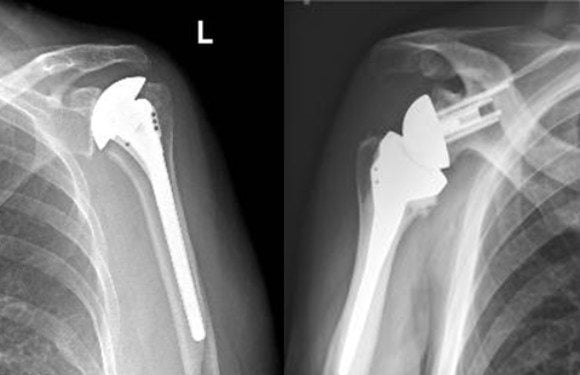

Вернуться к активной и привычной жизни поможет более эффективный способ хирургического воздействия при деформирующем артрозе плечевого сустава. Эндопротезирование – это сравнительно молодой вид оперативной коррекции, который позволяет заменить атрофированный больной сустав на его искусственный аналог.

Эндопротезы — цементные и бесцементные — различаются способом крепления к кости. В зависимости от заменяемых частей сустава различают два вида протеза:

- гемиартропластика, когда заменяется только головка плечевой кости;

- тотальный протез, когда необходима полная замена плечевого сустава.